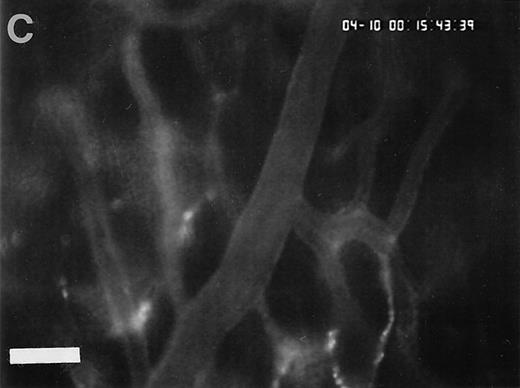

To assess fibrinogen deposition during I/R, the vascular distribution of fibrinogen was determined using immunohistology. In sham-operated animals small amounts of fibrinogen were detectable within the vessel lumen. Fibrinogen accumulation on the endothelial surface was not observed. In contrast, fibrinogen sequestration on the luminal surface of arterioles and venules was a prominent phenomenon after I/R. To investigate the time course of fibrinogen binding to the endothelial cell surface during I/R in vivo, fluorescent fibrinogen was administered intravenously before the induction of 1.5 hours of ischemia. In the physiologic state (baseline conditions), Alexa 488-conjugated fibrinogen was found homogeneously distributed in the plasma. No fibrinogen deposition was detectable in arterioles or venules (Fig 4). Similarly, during the ischemic period, no significant accumulation of fibrinogen on the endothelial surface was observed. In contrast, reperfusion dramatically enhanced fibrinogen binding to the endothelium in the postischemic microvasculature. Within 1 to 5 minutes after the onset of reperfusion, streaks of fluorescent fibrinogen were observed along the endothelial lining. After 10 minutes of reperfusion, the gaps between the streaks were partially filled with fibrinogen, resulting in a heterogenous fibrinogen coat on the endothelial cell surface of the majority of all vessels studied. In most instances, significant fibrinogen deposition at the arteriolar and venular endothelial surface coincided with the adhesion of platelets in these areas (Fig 4).

Accumulation of fibrinogen and platelets during I/R in vivo. Alexa 488-conjugated human fibrinogen (17 mg/kg) was administered intravenously 30 minutes before the induction of ischemia (left column). Rhodamin-labeled platelets were visualized in identical arterioles and venules using a different filter set (right column; see Materials and Methods). In wild-type animals (A,B), fibrinogen is bound unevenly to the vascular wall of arterioles and venules in the postischemic microvasculature. Areas with large amounts of fibrinogen (A, large arrow) can be seen besides regions without detectable fibrinogen deposition (A, small arrow). The accumulation of large amounts of fibrinogen colocalizes with platelet adhesion (B, arrowhead). In mice lacking ICAM-1 (C,D), the I/R-induced accumulation of fibrinogen and platelets is attenuated. Monitor magnification, 450×.

To determine the role of ICAM-1 as an endothelial fibrinogen receptor, the accumulation of Alexa 488-conjugated fibrinogen during I/R was investigated in mice deficient in ICAM-1. No fibrinogen binding was seen under control conditions or during ischemia. During reperfusion, a moderate increase in endothelial fibrinogen binding occurred in few arterioles and venules (Fig 4), while the majority of the vessels studied showed no significant fibrinogen accumulation, indicating that ICAM-1 is in fact involved in mediating the deposition of fibrinogen at the postischemic endothelium. To evaluate whether ICAM-1–dependent fibrinogen sequestration on the endothelial surface might mediate platelet-endothelial cell interactions during postischemic reperfusion, fluorescent wild-type platelets were infused into ICAM-1–deficient animals (Fig 1). Whereas the number of rolling platelets did not differ from wild-type mice (23 ± 5 and 36 ± 4 platelets/s/mm in arterioles and venules, respectively), platelet adhesion was significantly reduced in the absence of endothelial ICAM-1: 125 ± 42 and 71 ± 27 platelets were seen firmly attached per mm2 endothelial cell surface of arterioles and venules, respectively, indicating that ICAM-1 is in fact involved in platelet recruitment during postischemic reperfusion.